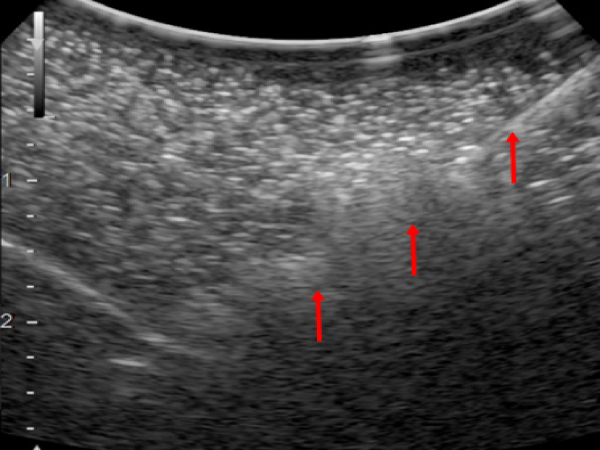

さらに当院ではフュージョンイメージングというCTやMRIなどの画像データをコンピュータで処理し、 超音波で描出されているのと同じ断面を作成して超音波画像と並べて比較することにより開腹せずに正確に腫瘍内部に器具を挿入することが可能です。

CT

超音波検査

赤矢印で示しているのが針(アンテナの先端)

実際の手術の様子(開腹はしない場合)フージョンイメージングを用いて超音波ガイド下で腫瘍に器具を挿入する